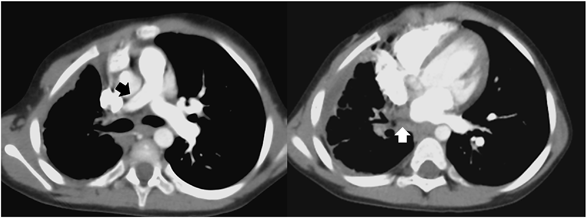

Fig. 2 Right pulmonary arterial wedge angiography in case 1

The blind right pulmonary vein was in close proximity to the wall of the left atrium. Furthermore, the end of pulmonary vein (arrow) was beating quite as if there was muscle tissue.